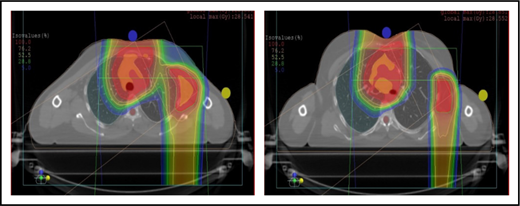

Proton therapy can significantly reduce the radiation dose to the breasts by specifically using fields that enter posteriorly and stop short of exiting through the breast. Alternatively, if protons cannot be used, other methods of displacing the breast can be used instead, such as using an inclined board or physically moving the breast out the beam path. Figure 3A shows how using proton therapy can spare the breast in a case with axillary involvement.

Axillary involvement at presentation. (A) Axial, coronal, and sagittal views of a proton plan (left) and an IMRT plan (right) for a patient presenting with axillary involvement. Use of proton therapy in this case spares the left breast. (B) Regardless of which treatment modality is chosen, IMRT (left panel) and proton (right panel), limiting the volume exposed to radiation should include attention to avoiding a low-dose bath. (C) Limiting lung dose. If avoiding the lung is the primary objective in a given patient, especially if the patient has received pulmonary toxic chemotherapy (eg, any combination of bleomycin, busulfan, gemcitabine, brentuximab, etc.), proton therapy may better spare the lungs by reducing the low-dose bath seen with photons.